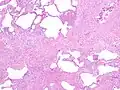

The histologic hallmarks of UIP, as seen in lung tissue under a microscope by a pathologist, are interstitial fibrosis in a "patchwork pattern", honeycomb change and fibroblast foci (see images below).[6][7]

Appearance of honeycomb change in a surgical lung biopsy at low magnification. The dilated spaces seen here are filled with mucin. Hematoxylin-eosin stain, low magnification. -